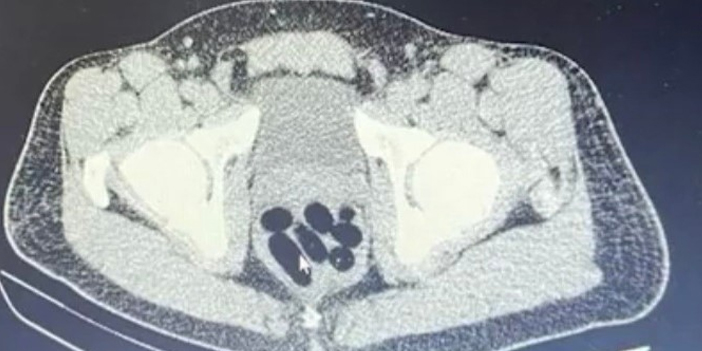

M.R.B'nin (23) kente uyuşturucu madde getireceğini tespit eden ekipler operasyon düzenledi. Gözaltına alınan şahsın hastanedeki iç beden muayenesinde 77 adet kapsül şeklinde 1 kilo 134 gram narkotik madde ele geçirildi.

Şahsın midesindeki maddeler cerrahi müdahale ile çıkarılırken, şahıs hakkında "uyuşturucu madde ticareti yapmak" suçundan adli işlem başlatıldı.